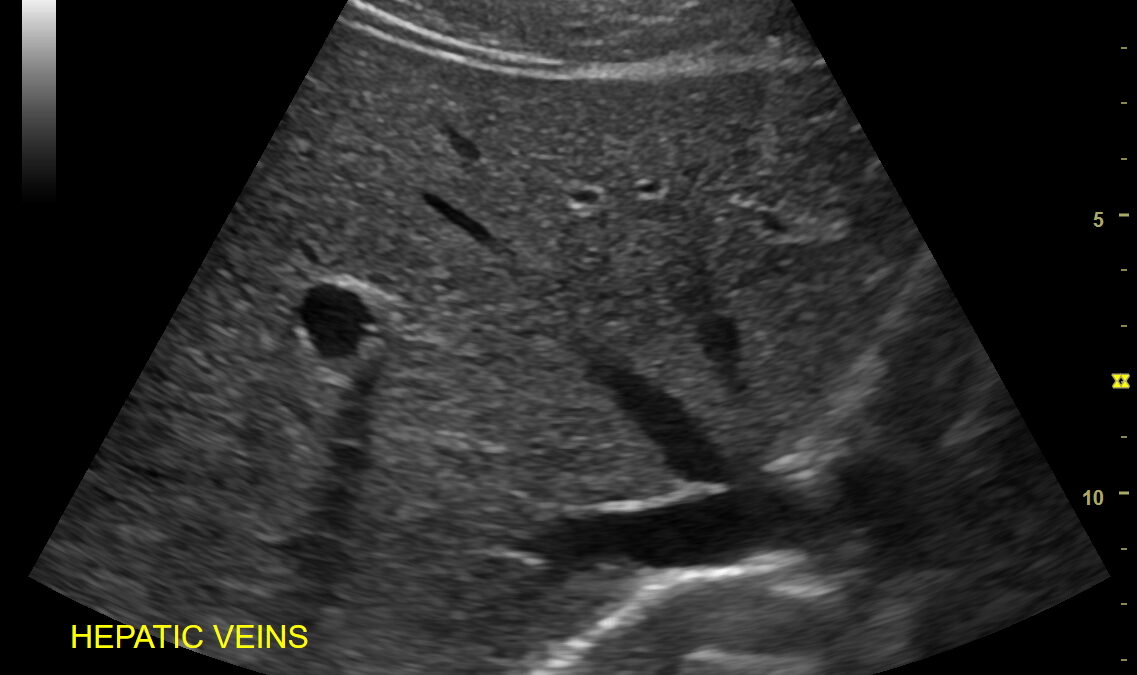

超音波(エコー)検査は、体の表面にプローブと呼ばれる機器を当てて、音波を反射させながら体内の臓器を映し出す画像診断法です。

腹部エコーでは、以下の臓器を中心に観察できます。

肝臓(脂肪肝・肝腫大・腫瘍など)

胆のう(胆石・ポリープ・胆のう炎)

膵臓(膵炎・腫瘤・膵管拡張)

腎臓(結石・水腎症・嚢胞)

膀胱・前立腺・子宮・卵巣など(性別に応じて)

検査時間は10〜15分程度。痛みもなく、その場で結果を確認できることが多いため、「すぐに原因を知りたい」「安心したい」という方に適しています。